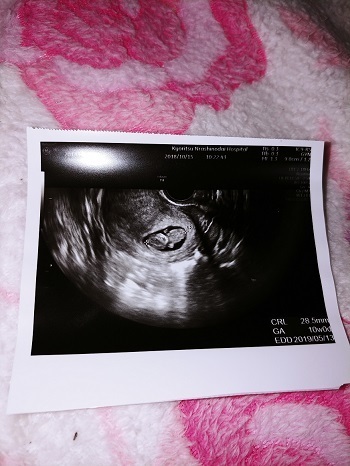

10週0日(10w0d・女の子)|しぃ~ちゃん さん(21歳)

エコー写真撮影時のエピソード:

このエコー写真が1番好きです!

まだちゃんと手の形にもなってなくてクリオネちゃんみたいな感じがたまらなく可愛いです!

赤ちゃんは7ヵ月検診の時に逆子ちゃんで565gと小さめです。私自身小さいのでそんなに気にしなくても大丈夫と先生は言ってくれていますがちゃんと大きく成長してくれるのか心配です。気になる症状はおっぱいが痒くて掻くと水みたいのが出てくることです。しかも日によってはブラがびちょ濡れになる時もあります。家族は早く会いたいと心待ちにしてます!